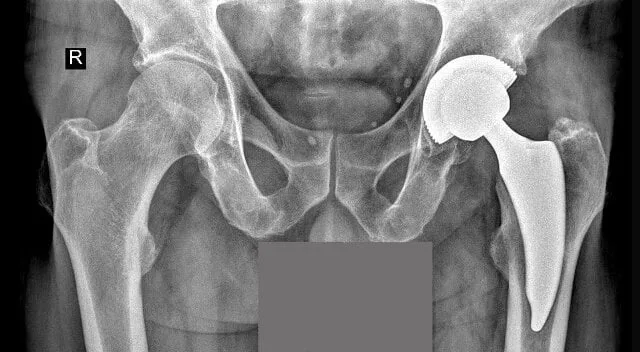

Wybór odpowiedniej placówki do wykonania endoprotezoplastyki stawu biodrowego w Polsce, szczególnie w ramach NFZ, jest kluczowy dla pacjentów oczekujących szybkiej i wysokiej jakości opieki medycznej. W ostatnich latach zauważalny jest rosnący popyt na zabiegi endoprotezoplastyki, co sprawia, że krótkie terminy oczekiwania oraz jakość świadczonej opieki stają się priorytetami dla pacjentów. W Polsce wyróżniają się dwie placówki: Medical Magnus Clinic w Łodzi oraz Szpital Św. Rafała w Krakowie, które oferują znacznie krótsze czasy oczekiwania niż średnia krajowa.

Wybór odpowiedniej placówki do wykonania endoprotezoplastyki stawu biodrowego w Polsce jest kluczowy dla pacjentów, którzy chcą skorzystać z usług NFZ. Warto zwrócić uwagę na krótkie terminy oczekiwania oraz jakość opieki medycznej, które mają ogromny wpływ na komfort i efektywność leczenia. W Polsce wyróżniają się szczególnie dwie placówki: Medical Magnus Clinic w Łodzi oraz Szpital Św. Rafała w Krakowie, które oferują znacznie krótsze czasy oczekiwania niż średnia krajowa.

W Medical Magnus Clinic średni czas oczekiwania na zabieg wynosi 180 dni, co jest znacznie lepszym wynikiem w porównaniu do średniej krajowej, wynoszącej 458 dni. Szpital Św. Rafała również wyróżnia się, z czasem oczekiwania wynoszącym 210 dni. Te krótkie terminy są możliwe dzięki nowoczesnym technikom chirurgicznym oraz dobrze zorganizowanemu procesowi leczenia, co czyni te placówki najlepszymi wyborami dla osób potrzebujących endoprotezy stawu biodrowego w ramach NFZ.

Szpital Św. Rafała w Krakowie to placówka znana z innowacyjnych metod leczenia i krótkiego czasu oczekiwania na zabieg endoprotezoplastyki stawu biodrowego, który wynosi 210 dni. Szpital realizuje zabiegi w ramach NFZ, co czyni go dostępnym dla pacjentów z różnymi potrzebami zdrowotnymi. W placówce stosowane są nowoczesne techniki chirurgiczne, takie jak małoinwazyjny dostęp przedni (DAA), co minimalizuje uszkodzenia tkanek miękkich i przyspiesza rekonwalescencję.